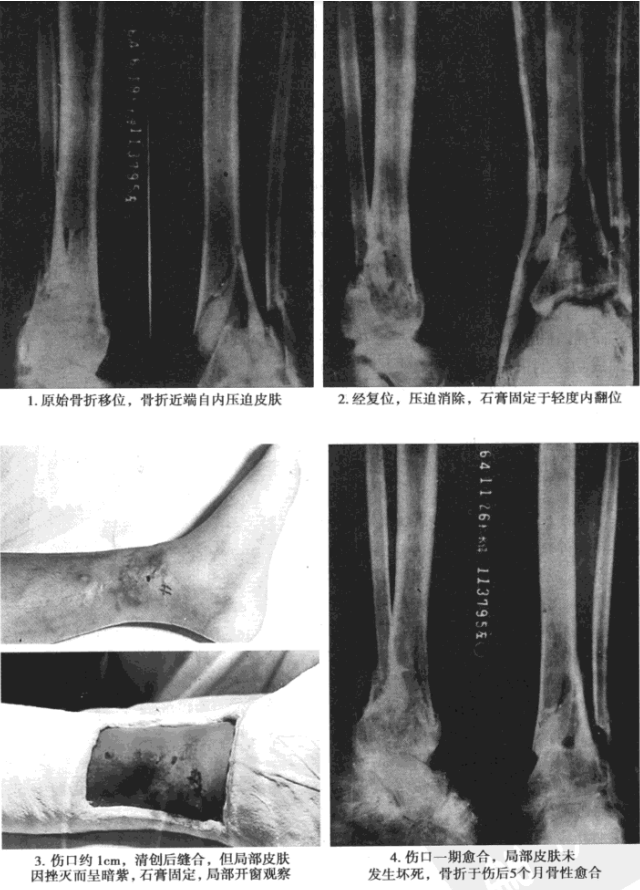

而有些则更接近于局部固定,例如小腿的侧方旋转石膏夹板,实为内前侧对外后侧夹板,仅其下端超过两踝;前臂的旋转石膏夹板,只包括腕关节(图7)。

△ 图7 局部石膏夹板